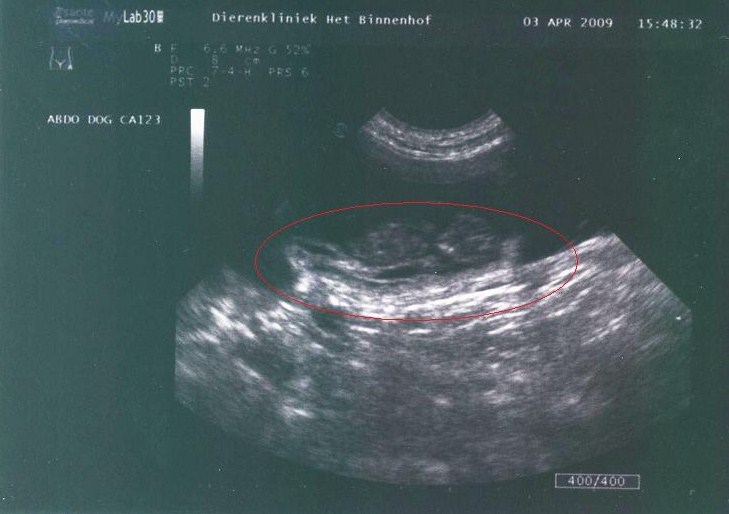

Cait loopt op het einde van haar dracht en is in topconditie. Hieronder dan eindelijk de echo (met wederom dank aan Karin Scholten!) met bewegende beelden die gemaakt is op 7 april jl. Klik op de foto om de echobeelden te zien....

Amai! Ze zit inderdaad vol!!!!  Gisteren weer een unieke ervaring meegemaakt (met dank aan Karin Scholten van kennel La Joie Blanche) We zijn samen met Caitlin een echo wezen maken waarbij de bewegende beelden zijn opgenomen. Caitlin is nu ongeveer 40 dagen drachtig van onze Caronne en men kon nu ook de orgaantjes, ruggegraat en zelfs het verschil zien tussen reuen en teven.

2e echo Caitlin

2e echo; de pupjes zijn aardig gegroeid in 1 week

Pup in vruchtblaasje

Een vruchtblaasje waarin duidelijk een pup te zien is